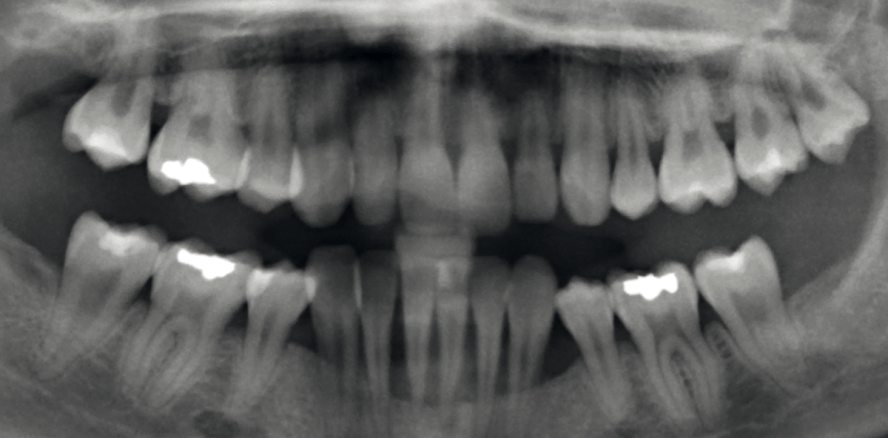

Abb. 1

Obwohl parodontalpathogene Bakterien für die Entstehung der Parodontitis essenziell sind, gibt es genügend Menschen, die keine Parodontitis entwickeln, obwohl sie mit Parodontalpathogenen infiziert sind. Jeder Mensch hat nämlich eine individuelle, dosisabhängige Immunantwort auf den bakteriellen Angriff. Die Art und Stärke, wie das Immunsystem auf den bakteriellen Angriff reagiert, ist genetisch determiniert. Bei der Parodontitis handelt es sich daher um eine komplexe Erkrankung. Viele Genvariationen sind an der Entstehung der Erkrankung beteiligt sind und beeinflussen sich gegenseitig. Genetische Veränderungen können auch einen schützenden Effekt haben. Schützende und krankheitsfördernde genetische Anlagen und zusätzliche nicht- genetische Risikofaktoren wie Rauchen oder Stress mischen sich somit zu einem individuellen Krankheitsrisiko. Die genetische Prädisposition gibt den Rahmen für das Gesamtbild vor, das durch Umwelteinflüsse modifiziert wird (multifaktorielle Genese) (Abb. 1).

Abb. 2: : Parodontitis ist eine komplexe Erkrankung. Schützende und krankheitsfördernde genetische Varianten und zusätzliche Risikofaktoren wie Rauchen oder Stress mischen sich zu einem individuellen Krankheitsrisiko. –Abb. 3: Ehlers-Danlos-Syndrom Typ VIII. Typische Merkmale sind eine schwere Parodontitis im Teenager- oder frühen Erwachsenenalter und die Überdehnbarkeit der Fingergelenke.